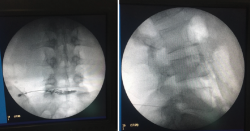

Constituye una evaluación radiológica (bajo control fluoroscópico) y fisiológica del disco intervertebral mediante, la inyección intradiscal de un medio de contraste, ya sea por vía intra- o extradural. Hay que tener en cuenta la cantidad de contraste que ha sido inyectado, la presión de inyección, el aspecto radiológico del disco inyectado y, por último, la reproducción de dolor durante la prueba.

La inyección de contraste en un disco intervertebral normal es habitualmente indolora y el contraste tiende a permanecer en el núcleo pulposo, por lo que se considerará positiva esta prueba cuando la inyección intradiscal provoca un dolor semejante al referido por el paciente y la morfología del discograma es anormal o se produce la extravasación del contraste utilizado.

Figura 15. Discografía.

La técnica consiste en pinchar oblicuamente con una aguja en el centro del disco e introducir un contraste radiopaco. El enfermo está despierto en todo momento. Con ese contraste radiopaco se produce una imagen clara de si el disco es o no patológico, pudiendo apreciar si el disco entre vértebra y vértebra está deshidratado, si la morfología es normal o diferente, si sale o no contraste, si hay dolor irradiado a ambas piernas o solo a una de ellas, y si ha notado o no dolor el paciente (Figura 15).

La discografía es utilizada como método diagnóstico del dolor discogénico, aunque varios metaanálisis demostraron una disminución de la tasa de falsos positivos del 0 al 10%. La discografía es una prueba subjetiva, confiando completamente en la experiencia de dolor del paciente durante la realización de este breve procedimiento. Entre los elementos que disminuyen la tasa de falsos positivos se encuentra la utilización de criterios de inclusión más estrictos y la monitorización de la presión intradiscal.